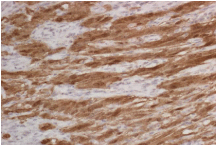

Final histologic sections of the excised esophageal mass show a submucosal proliferation of spindle cells with elongated nuclei with bland nuclear features (Figure 2 and 3). There are numerous admixed reactive lymphoid follicles. Focally, there is a suggestion of Verocay body formation (Figure 4). Antoni A and B tissue types are also visible in these sections. Immunohistochemical stains demonstrate that these spindle cells stain with S100 (Figure 5) and SOX-10. Stains for CD34, CD117, Actin, AE1/ AE3, Desmin, and DOG-1 are negative within the spindle cells.The negative reactivity for CD34 and CD117 rules out a gastrointestinal stromal tumor (GIST) and negativity for Actin and Desmin stains distinguishes the tumor from the more common leiomyoma. A stain for STAT6 is negative and a stain for neurofilament does not highlight axon within the lesion. Overall these findings are diagnostic for Schwannoma. There are no features to suggest malignancy.

Figure 5: S100 Staining.